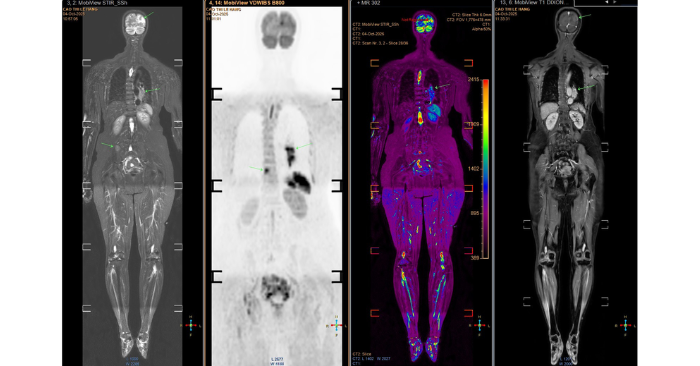

Kết quả MRI cho thấy nhiều ổ tổn thương di căn dạng biểu mô tuyến. Hình ảnh CT xác nhận khối u lớn ở đáy phổi trái, lan lên não, cột sống và xương chậu.